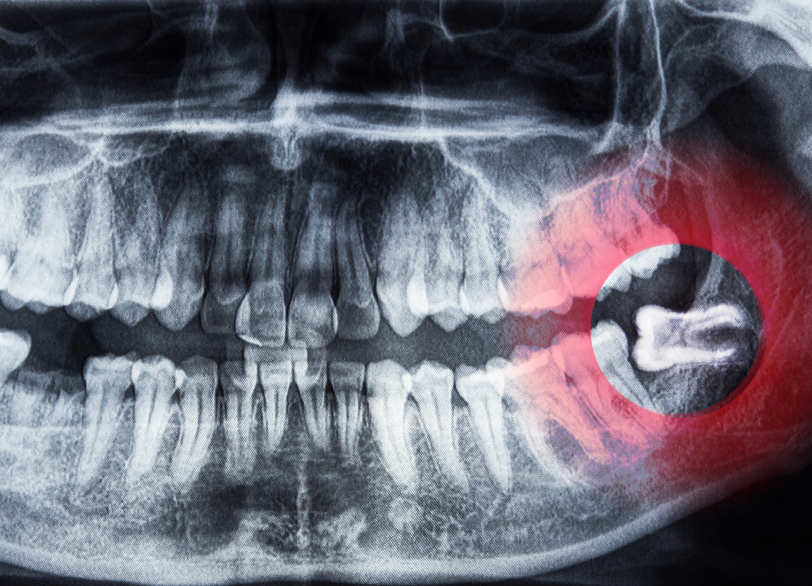

親知らず(第三大臼歯)は、永久歯の中で最も遅く、10代後半から20代前半頃に生えてくる一番奥の歯です。

しかし、食生活の変化によって現代人の顎は小さく進化しており、親知らずが正常に生えるためのスペースが不足しています。

その結果、斜めに生えたり、横を向いて埋まったり、手前の歯に引っかかって途中までしか出てこなかったりと、正常な位置に生え揃わないケースが大半を占めています。

親知らずの抜歯、特に下の親知らずの抜歯においては、事前の診断が安全性を左右します。

下の親知らずの根の近くには、「下歯槽神経(かしそうしんけい)」という太い神経と血管が通っています。

万が一、抜歯の際にこの神経を傷つけてしまうと、唇や舌にしびれ(麻痺)が残ってしまうリスクがあります。

従来のレントゲン写真は2次元(平面)であるため、親知らずと神経が重なって写ることがあり、正確な距離感を把握することが困難でした。

そこで当院では、抜歯の難易度が高いと判断される場合には、必ず「歯科用CT」による撮影を行います。

CTは3次元(立体)の画像を得ることができるため、親知らずの根の形や曲がり具合、そして神経との位置関係を0.1ミリ単位で正確に把握することができます。

「神経に触れているか、離れているか」を事前に知ることで、安全なアプローチ方法を計画し、偶発的な事故を未然に防ぐことが可能となります。